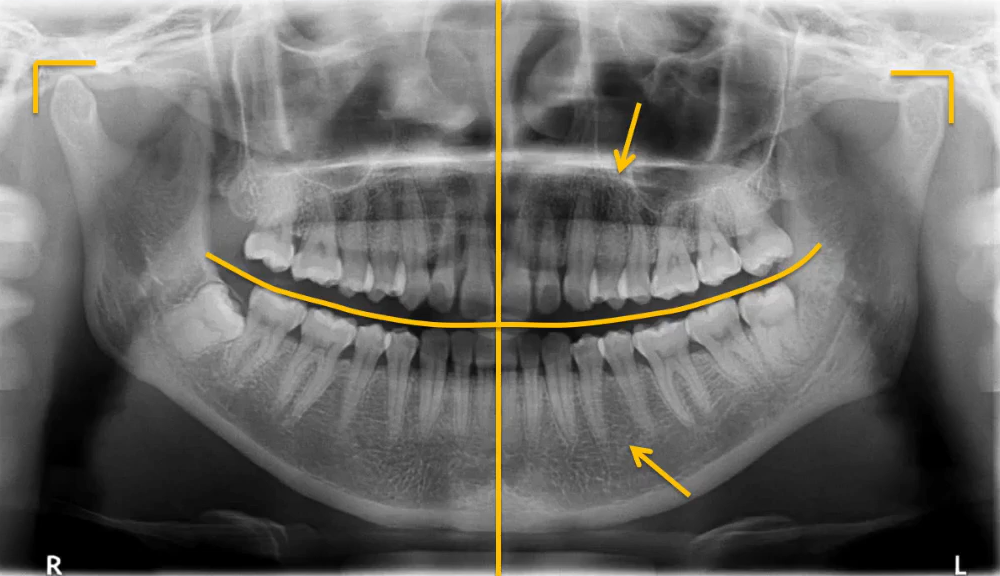

1. 先整体后局部,有顺序不遗漏

因为曲面断层片反映的是上下颌牙齿、上颌窦、关节,在一张片子中所展示的解剖结构较多。比如刚才的片子,最容易诊断的是右下6远中邻面深龋合并根尖周炎,左下有埋伏的多生智齿,右侧是垂直智齿。

注意不要遗漏,比如片子中显示上颌两个3是缺失的,是先天性缺失还是做过手术?有可能会漏掉一些临床信息。

2. 推荐象限顺序

1(右上)→2(左上)→3(左下)→4(右下)

3. 推荐检查部位顺序

牙→骨→上颌窦→关节

比如患者右侧髁突的前斜面发生了硬骨改变。

4. 左右对称比较

左、右下5根方有低密度影,一般认为是颏孔位置,左右对称进行观察可以排除一些疾患。